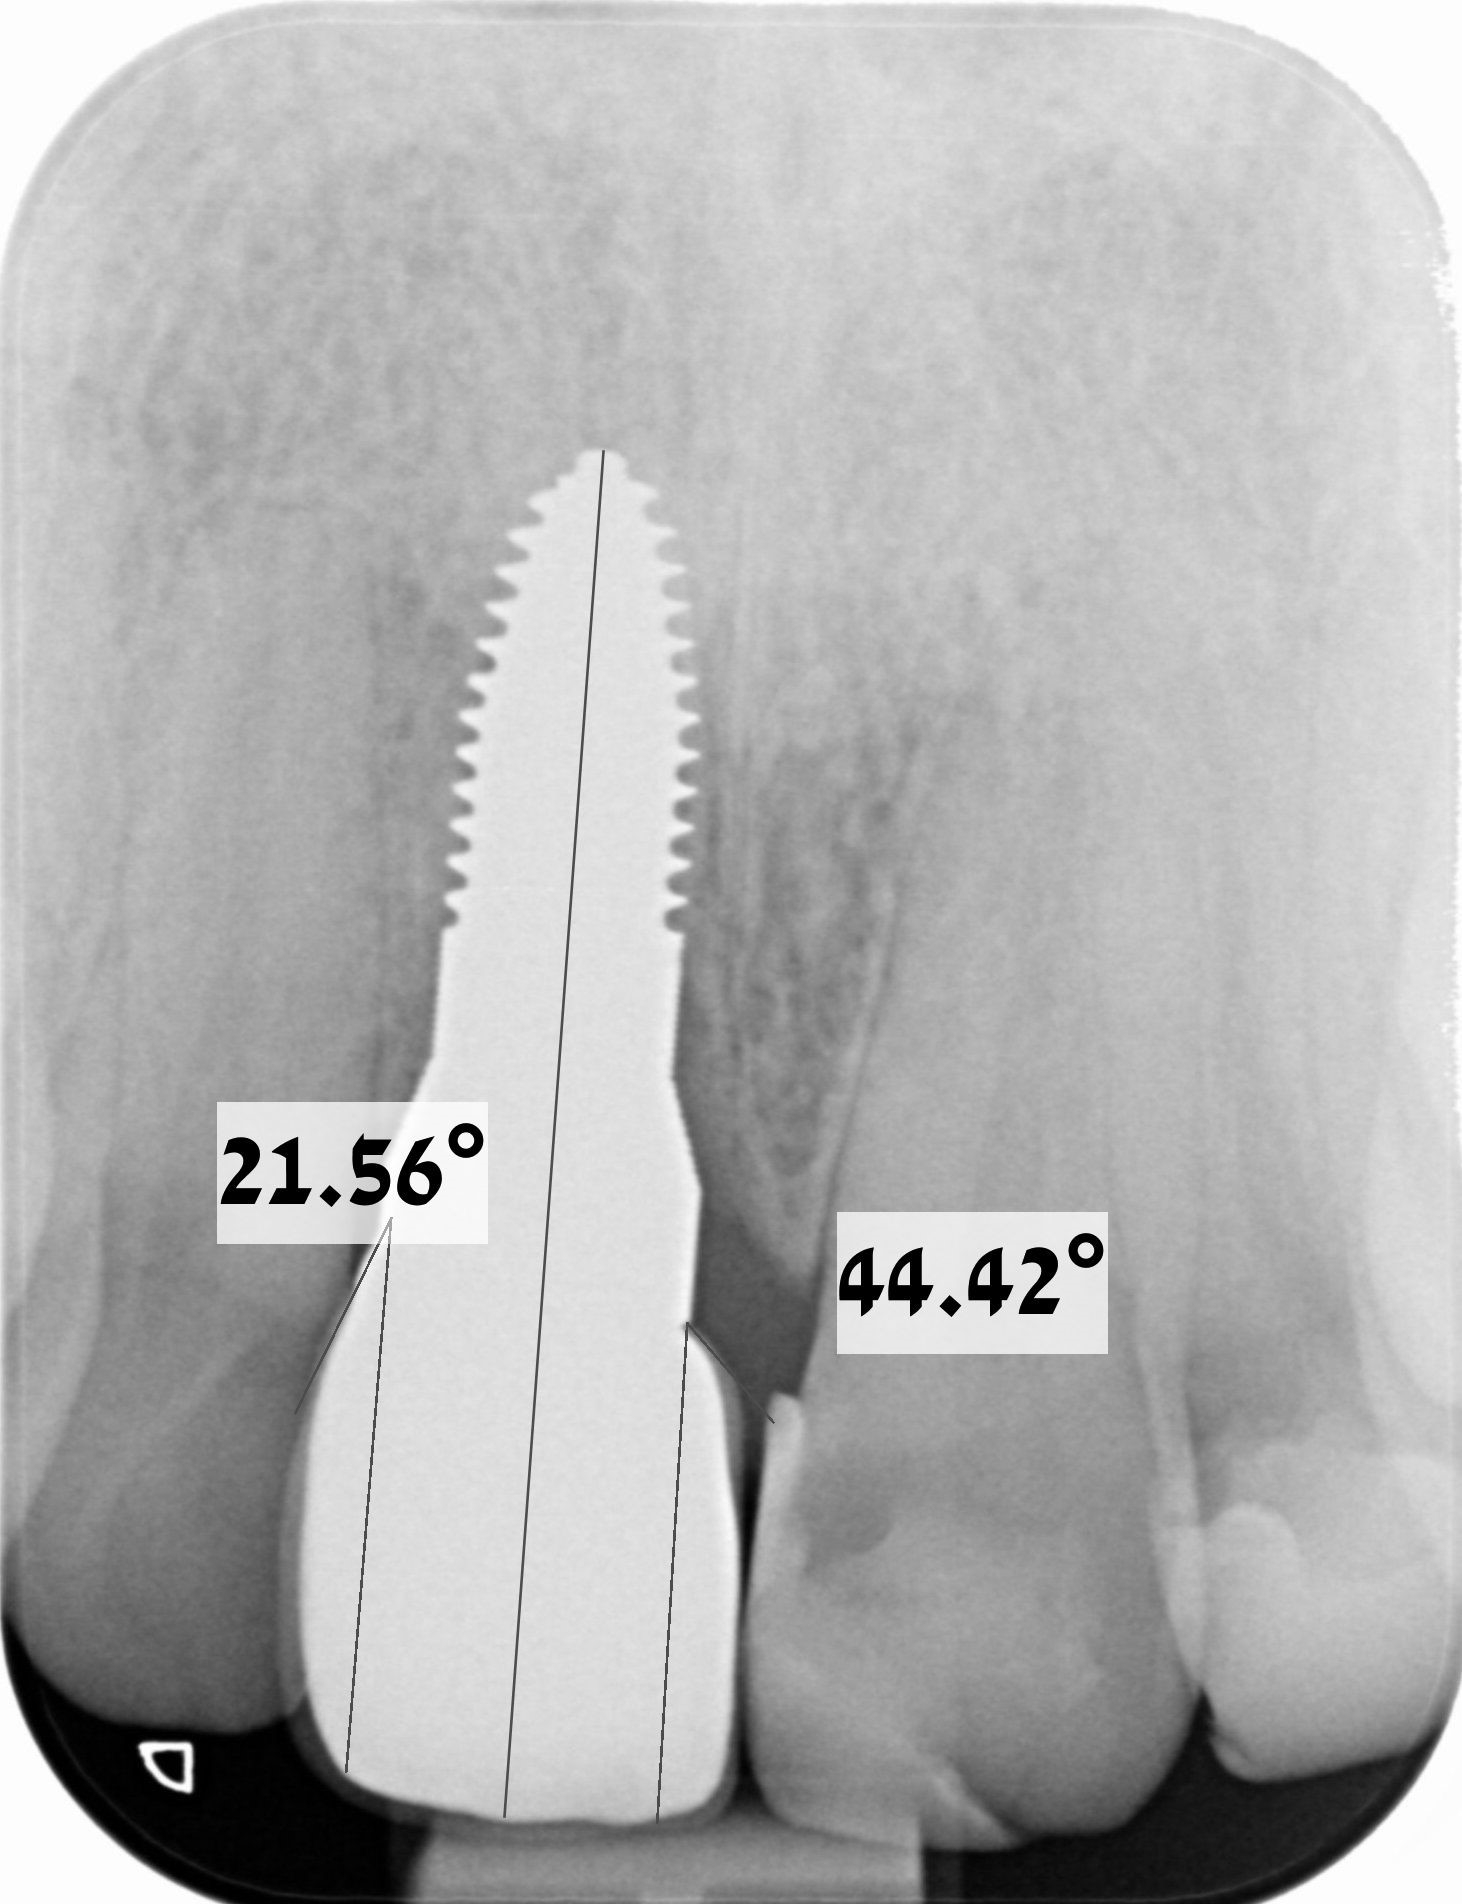

Methods: One examiner recruited and examined 70 patients, each of them exhibiting a dental implant with a contralateral tooth. Thirty-five patients contributed one titanium implant of various types and 35 patients a zirconium implant each. Periodontal and peri-implant probing depths (PPD) and clinical attachment level (CAL) were assessed. Whether implant or tooth was measured first was randomly assigned. Immediately after probing patients scored discomfort/pain using a visual analogue scale (VAS). The emergence profiles of implant crowns were assessed as transitional contour relative to the long axis on periapical radiographs of the implants.